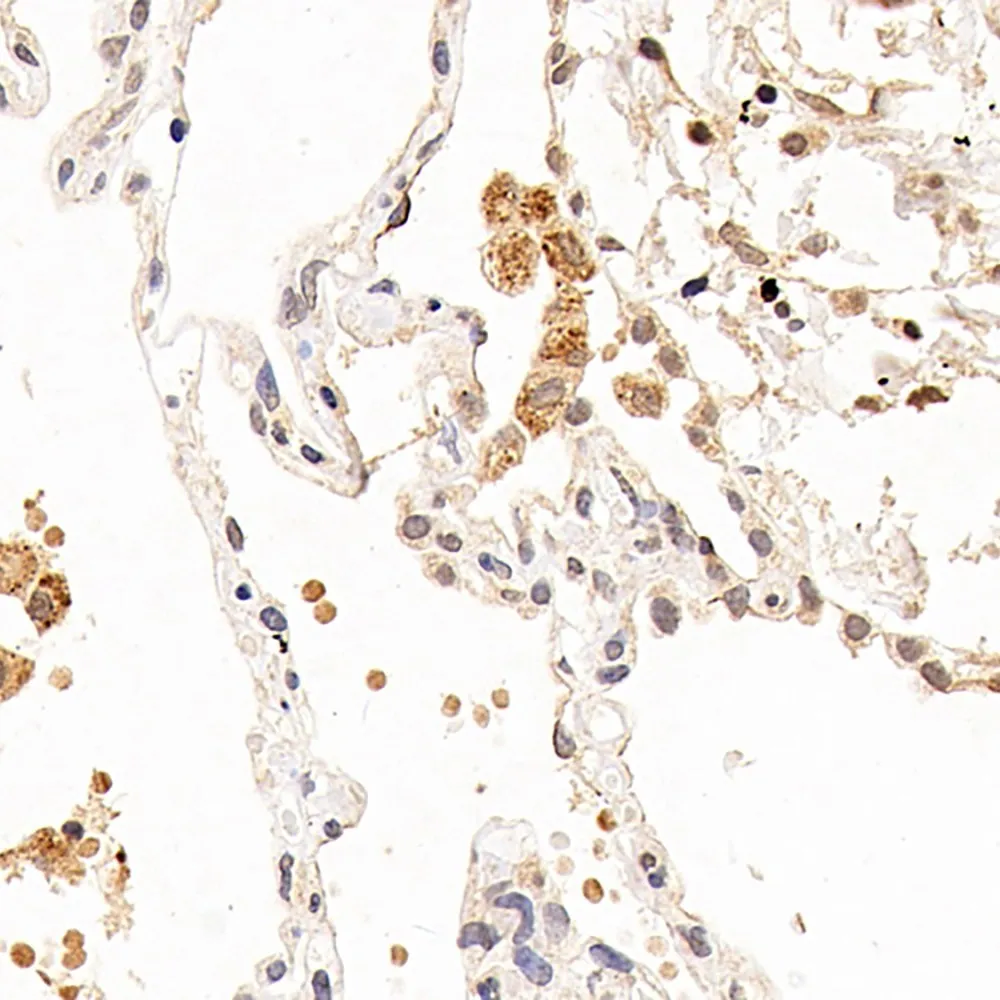

CXCR7 Polyclonal Antibody

- Applications: IHC